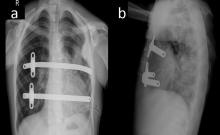

[4]Figure 2. Postoperative chest radiographs showing the bar positions in anteroposterior (a) and lateral (b) projections.

The authors decided to perform synchronous ASD closure and correction of the pectus excavatum deformity. The patient was placed in the supine position with the arms abducted to expose the anterior and lateral chest wall. The deepest point and the bilateral highest points (thoracic entry and exit points) of the thorax were marked. Two bars were used to correct the deformity. In total, four skin incisions were made: in the third intercostal space on the left side, in the fourth intercostal space in the anterior axillary line, in the third intercostal space on the right side, and the fourth intercostal space in the anterior axillary line on the right side. Subcutaneous pockets (two left and two right) were made by blunt dissection, and a median sternotomy was performed. The introducer was slowly advanced across the anterior mediastinal space immediately under the sternotomy. Using the introducer, a strand of cloth tape was pulled through the tunnel. The tape functioned as a guide for placement of the pectus bars, and then the pericardium was opened. The patient was put on cardiopulmonary bypass, the superior and inferior vena cavae were clamped, and the aorta was clamped. Cardioplegia was administered. The ASD was closed with a pericardial patch and cardiopulmonary bypass was terminated. Sternal wires were placed for sternal closure, but were not twisted. The introducers were linked to the tape and two bars were inserted with the convexity facing posteriorly, and the sternal wires were twisted. A bar flipper was used to turn the two bars over while pulling up the sternum. The rotated bars were fixed with butterfly stabilization on the right sides of the chest, and were fixed with PDS sutures on the left side (Figure 2). There was no need to use a thoracoscope, because the authors were able to see the procedure under direct vision through the sternotomy. The incisions were closed and the patient was taken to the cardiac intensive care unit with a mediastinal and two thoracic (left and right) chest tubes.